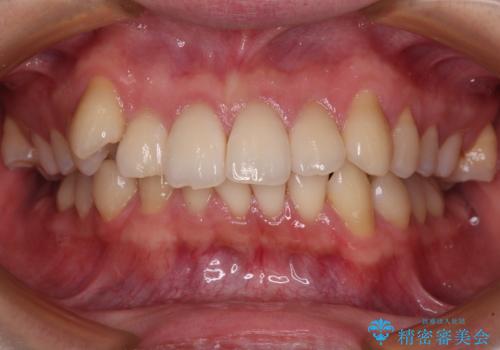

- 前歯のデコボコや八重歯を気にして来院された患者様です。

左右ともに奥歯の咬み合わせに問題があり、上顎臼歯が前方位にある状態で、結果として上顎前歯全体が前方位かつ叢生になっていました。

上顎のみの抜歯矯正であったため、治療期間が長期化することが予想されましたが、何とか3年弱の期間で想定通りの仕上がりで終えることができました。